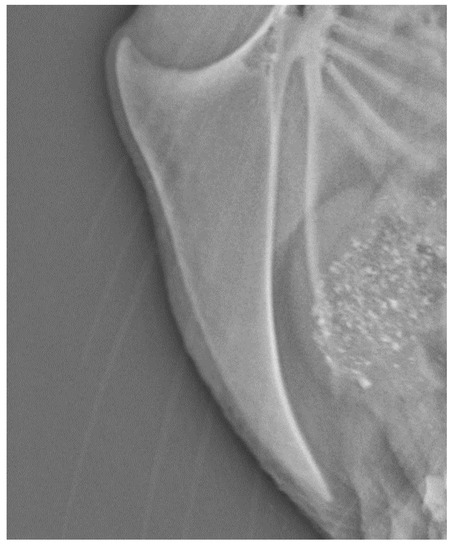

3. Results